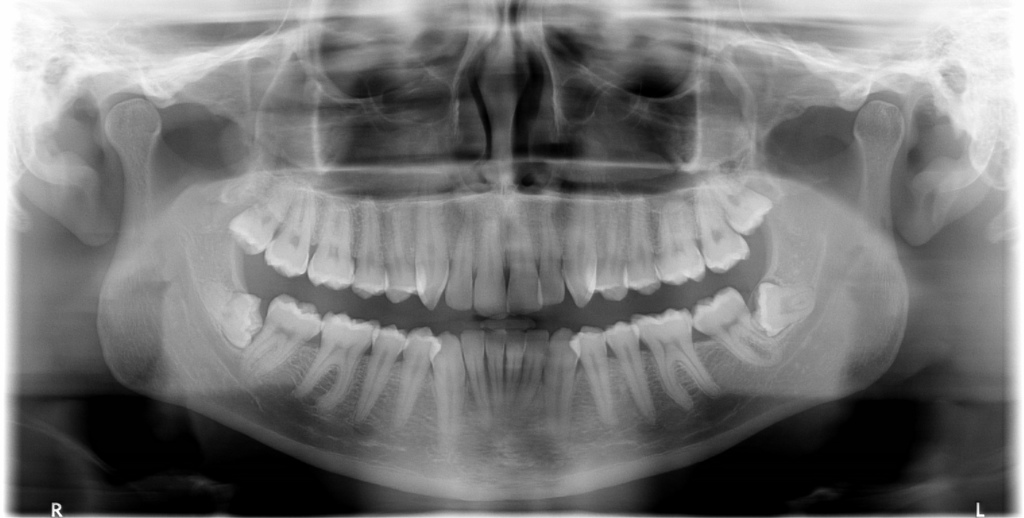

The most common X-Ray required is an OPG, which will show all the wisdom teeth, it will reveal signs of infection or other pathology, it will highlight the relation of the wisdom tooth to the adjacent molars and will show the proximity of the roots of the wisdom tooth to the inferior dental nerve.